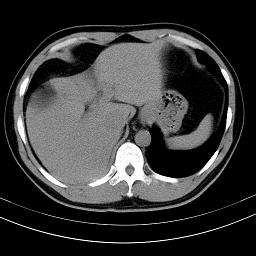

标题: CT18388:肝脏膈肌间隙内大量脂肪密度影 [打印本页]

标题: CT18388:肝脏膈肌间隙内大量脂肪密度影

是脂肪不是气体,有时候会碰到这样的病人,脂肪过多吧。

腹腔脂肪沉积过多

膈下脂肪沉积。

考虑膈下脂肪沉积。

激素治疗的病人容易脂肪沉积